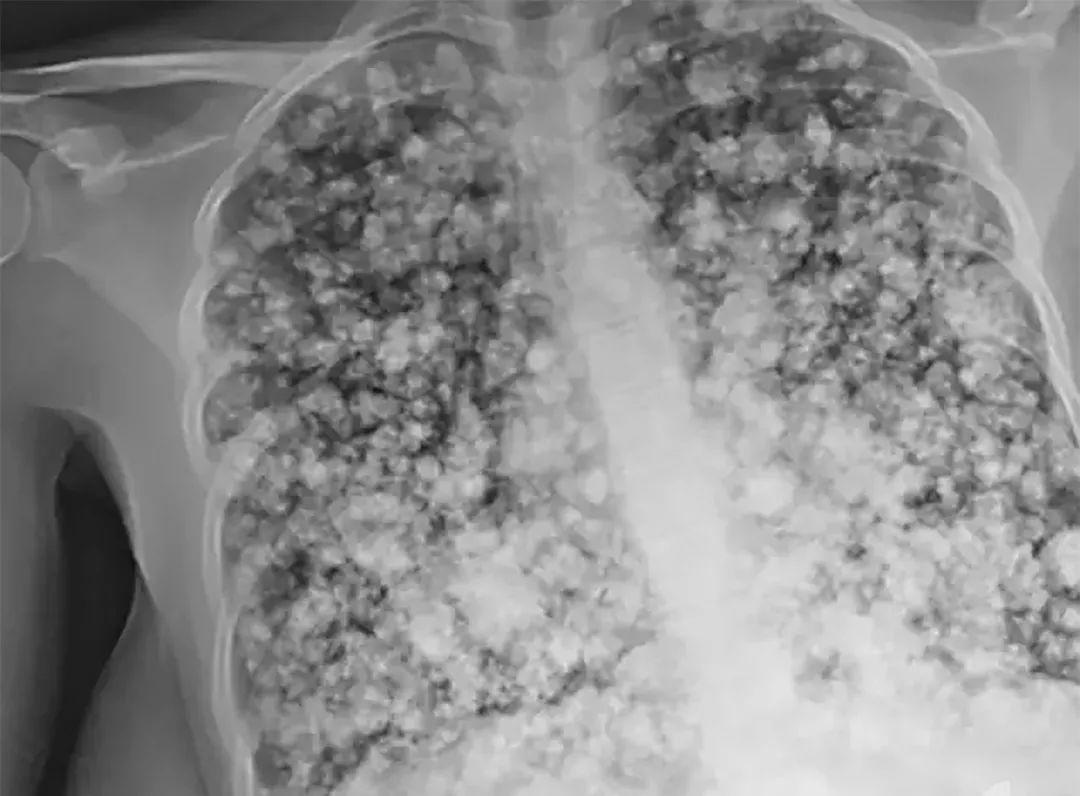

17岁少年肺被炸成爆米花,罪魁祸首也许你家也有!最近,被称为“戒烟神器”的电子烟,频繁登上热搜。 17岁加州少年因连续吸食电子烟,整个肺差点废了!

少年因咳嗽入院,本以为只是风寒,但检查结果出来,医生发现他的肺部已经成了“爆米花肺”。

仅仅几个小时后,少年就开始呼吸困难,全身插满了管子。 更可怕的是,医生诊断他的肺已经无法救治,只能进行双肺移植,就算手术成功,可能也只有5-6年的生命…… 5个月前还活蹦乱跳的高中生,人生就此改写,罪魁祸首就是:尼古丁! 少年并不知道,电子烟,并没有想象中那么友好。 虽然电子烟通过加热丝,把烟油雾化成水蒸气供人吸取,不会产生焦油和一氧化碳。 看似很健康,但元凶尼古丁的含量并不比普通香烟低,有些还可能超量! 频繁吸电子烟,有可能导致呼吸急促,哮喘,咳嗽,疲劳,甚至危害生命。 请大家一定要警惕这个香烟界的“新宠”,不要因为它换了个外壳,就掉以轻心。 毕竟,这些年来,被香烟害惨的孩子,太多了…… 看过这样一个揪心的新闻: 山东济宁一个8岁的女孩,被确诊为肺癌晚期。